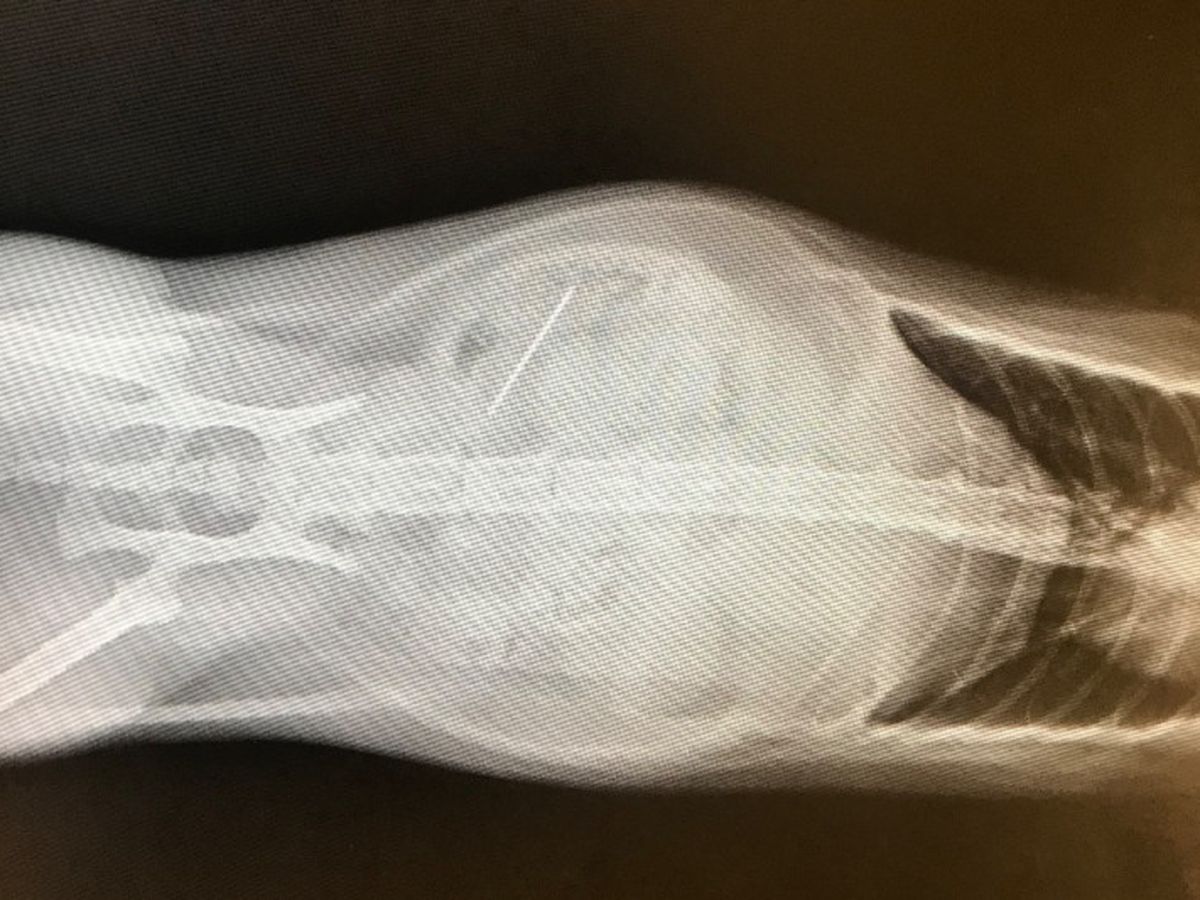

Our dear sweet Ratt in her infinite quest to eat everything has swallowed a sewing needle which became lodged in her small intestine. The needle is causing her infections and punctures and needs to be extracted by emergency surgery.